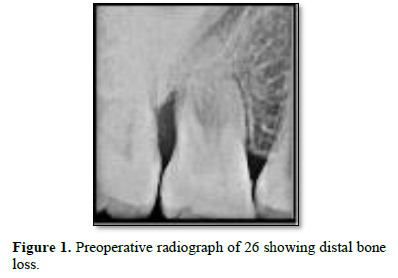

The clinical examination revealed periodontal pocket measuring 4mm distobuccally and 8 mm pocket distolingually with tooth 26 and 5mm pocket distobuccally with 36. Bleeding on probing was observed with both the teeth at distal aspect. No mobility was recorded with both teeth. Both teeth were non vital when tested with electric pulp test. Rest all dentition had normal periodontium. Radiographic examination revealed vertical bone loss till apex of distobuccal root of 26 (Figure 1) and vertical bone loss till apex of distal root of 36 (Figure 2).

Distal aspect of 26 and 36 presented bone loss right up till the apex of the closest root. This would have led to necrosis of the teeth. Complete curettage after flap reflection resulted in smooth surface of cementum. DFDBA was used as a graft material due to its osteoinductive nature. Studies have shown promising results in repair of furacation and periodontal defects. It also has ability to stimulate cell attachment and cell migration and osteogenesis [5]. Plasma rich fibrin membrane was used as a barrier to prevent formation of long junctional epithelium. It has growth factors and act as a matrix for migration of endothelial cells and fibroblast thus promoting angiogenesis and also promotes formation of more resistant connective tissue [6]. Six months follow up radiograph shows optimum bone formation with distobuccal root of 26 and partial bone formation with distal root of 36 suggestive of healing lesion. There was also reduction in probing pocket depth and gingival healing. Similar findings were reported by George PM in 2017 with use of Osseo graft in endo-perio lesion. Six months follow up revealed improved clinical and radiographic findings [2].